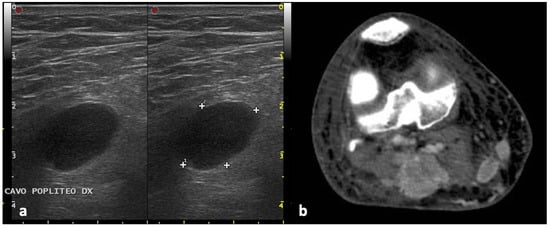

2.4. Ultrasound Assessment

2.5. Assessment with Other Imaging Techniques (CT, MRI, PET)